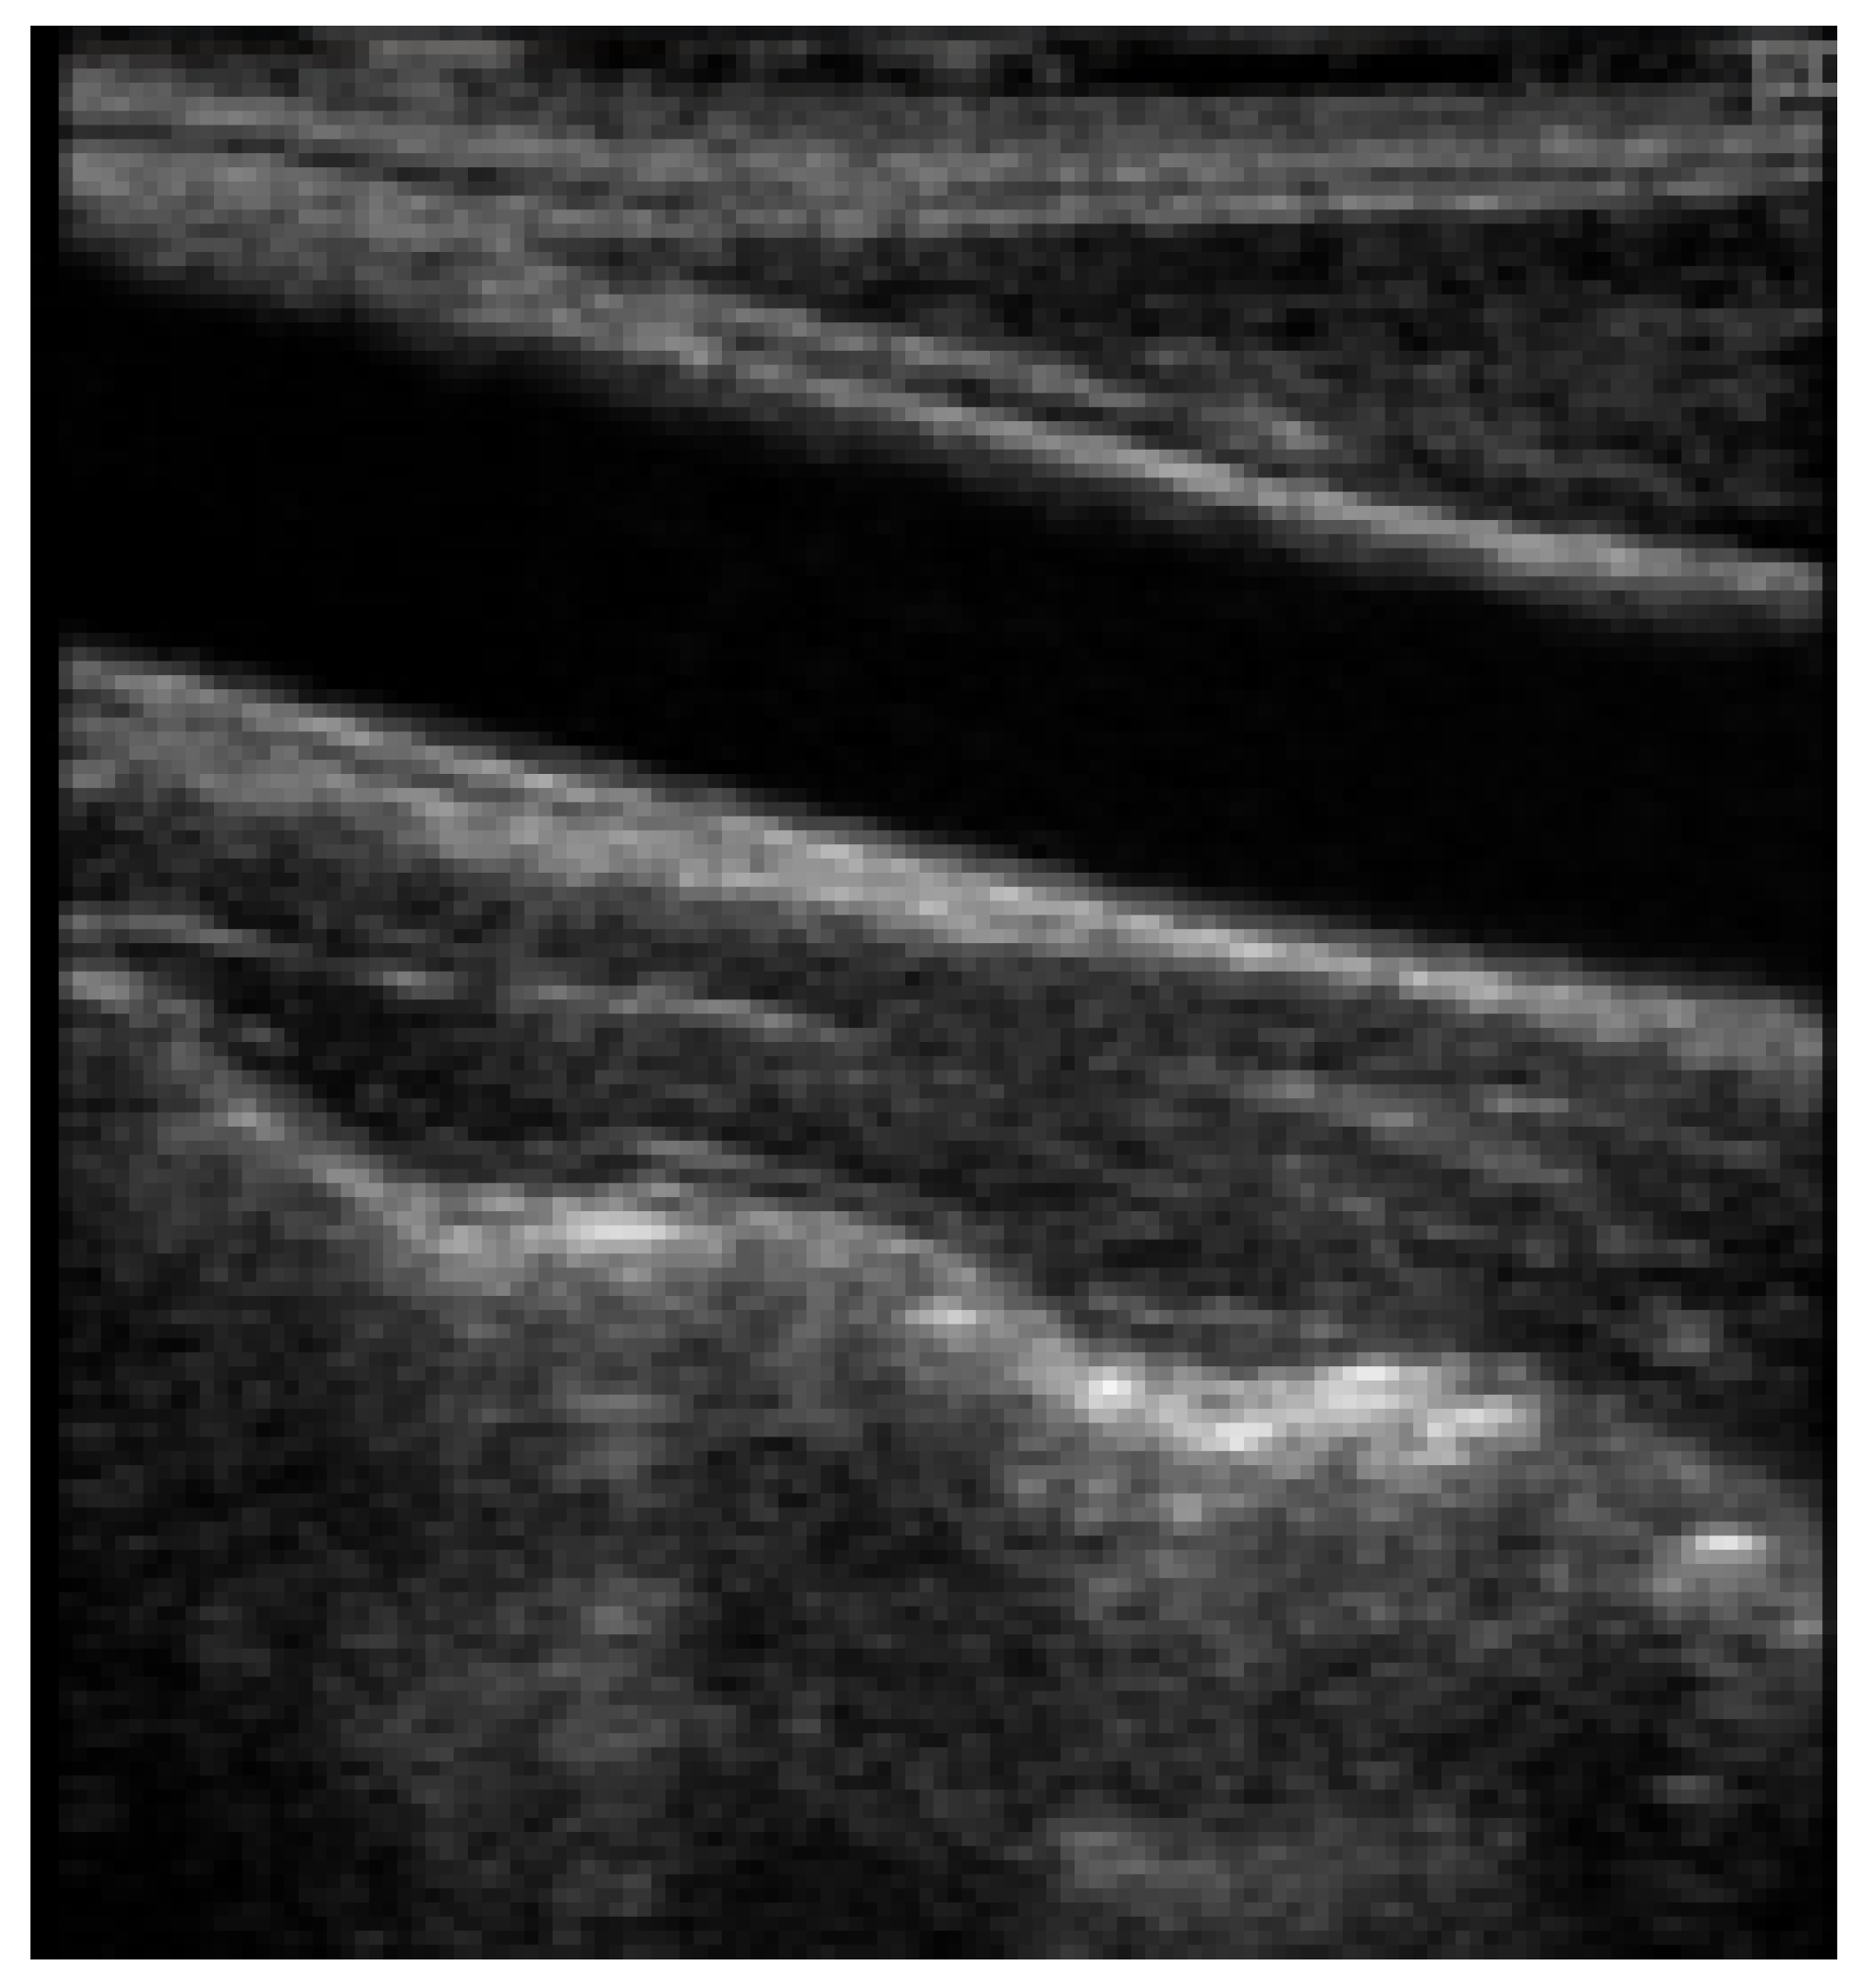

In 1986, Pignoli et al. [29] introduced the first computerized method for IMT segmentation of images acquired from ultrasound images. Later in 1990, the edge detection technique was implemented by Touboul et al. for IMT segmentation, which produced a good correlation compared to the ground truth [6]. Prior to that in 1988, advanced analysis techniques were performed on several imaging tools consisting of Magnetic Resonance Imaging, Computed Tomography, pulse wave, Doppler ultrasound, etc., for segmentation of the region of plaque and grading stenosis [3]. Furthermore, empirical examinations on in vivo and in vitro subjects, including both human and animal studies, have shown that the deposit of atherosclerotic plaque results in the dilation of the arterial wall and does not change the luminal size of the artery, allowing the arterial wall to be evaluated using these modalities [29]. Other than image processing, spectral analysis is conducted on Doppler US signals [30]. From then on, several imaging techniques such as MRI, CTA, DSA, Doppler waveform, B-mode ultrasound, etc., were widely implemented and analyzed. Figure 5, shows a B-mode ultrasound-generated image of the carotid artery region from the dataset published for public usage by Meiburger et al. in [31].

CUBS dataset: The dataset consists of 1088 patients from two different institutions. The correlation parameters were measured by skilled analysts who segmented the US images. The comparison with automated segmentation was positive. This dataset was annotated for intima–media thickness, and ground truth was provided by manual as well as automatic segmentation methods. The first version of the dataset consists of 2716 images, and the second version by the same authors consists of 500 images of the carotid artery. These datasets are publicly available in [31,76]. Figure 6 is a sample of the dataset with the intima–media mask.